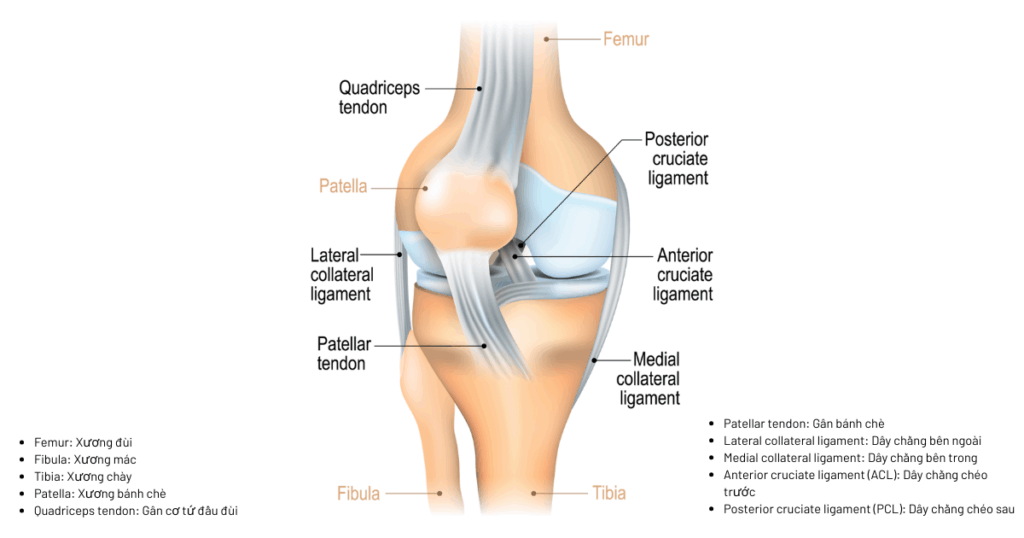

Khớp gối là nơi kết nối giữa ba xương: xương đùi, xương chày và xương bánh chè. Để những cấu trúc này phối hợp linh hoạt mà không lệch khỏi trục, cơ thể sử dụng một hệ thống gồm bốn dây chằng chính, thường được gọi là “bộ tứ dây chằng khớp gối”:

- Dây chằng chéo trước (ACL – Anterior Cruciate Ligament): ngăn xương chày trượt ra trước so với xương đùi.

- Dây chằng chéo sau (PCL – Posterior Cruciate Ligament): ngăn xương chày trượt ra sau.

- Dây chằng bên trong (MCL – Medial Collateral Ligament): kiểm soát lực lệch vào trong (gập vẹo khớp về phía chân trụ).

- Dây chằng bên ngoài (LCL – Lateral Collateral Ligament): kiểm soát lực lệch ra ngoài (vẹo khớp khỏi trục).

Bốn dây chằng này phối hợp như một “bộ khung sinh học” giúp khớp gối giữ được độ ổn định trong tất cả các hướng di chuyển: trước – sau, trong – ngoài, xoay – gập. Nhờ đó, chúng ta có thể chạy, bật nhảy, ngồi xổm hay đổi hướng một cách an toàn và chính xác.